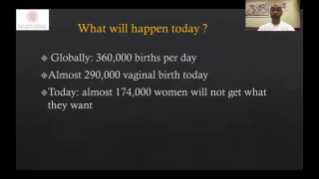

Geoptimaliseerde workflows in gynaecologie en verloskunde zijn noodzakelijk ter ondersteuning van grote pati?ntenvolumes aan screeningbezoeken voor vrouwen. Misvormingen van het centrale zenuwstelsel (CZS) zijn bijvoorbeeld een van de meest voorkomende aangeboren afwijkingen. Als gevolg van verschillende beeldvormingscondities, zoals een slechte foetale positie, is de MSP zeer moeilijk te vinden in een 2D-echografie. Daarom kunnen geautomatiseerde detectie en metingen de scaneffici?ntie sterk verbeteren.